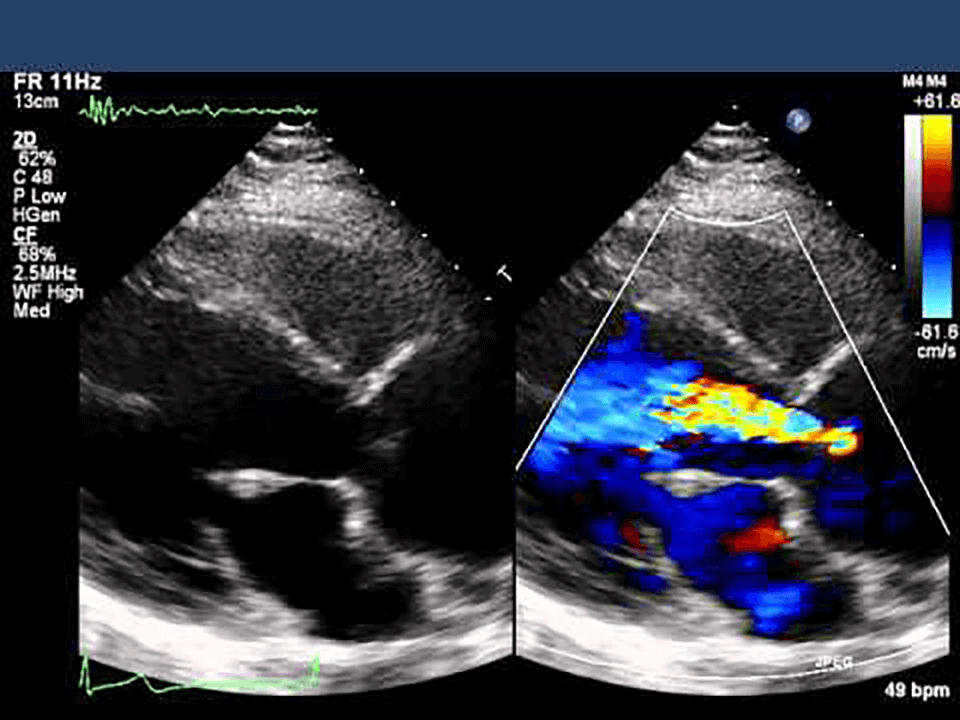

超音波(人の耳には聞こえない高い周波数の音波)を体の表面にあて、体内の臓器を画像化し、臓器の形態や血流情報をリアルタイムに観察する検査です。

心臓の大きさや動き、弁の異常、心臓内の血流の状態などを観察します。

心筋障害や弁膜症などの心疾患の診断、心機能の評価に役立ちます。

胸壁にプローブ(超音波を送受信する部分)をあて、体の表面から心臓を観察します。